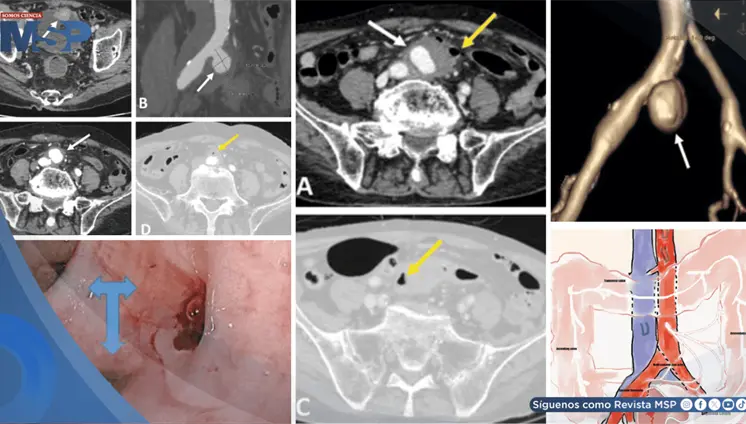

La trombosis de la vena espermática está asociada a enfermedades inflamatorias intestinales, como la colitis ulcerativa y la ileítis terminal, que generan un estado protrombótico debido a su naturaleza inflamatoria.